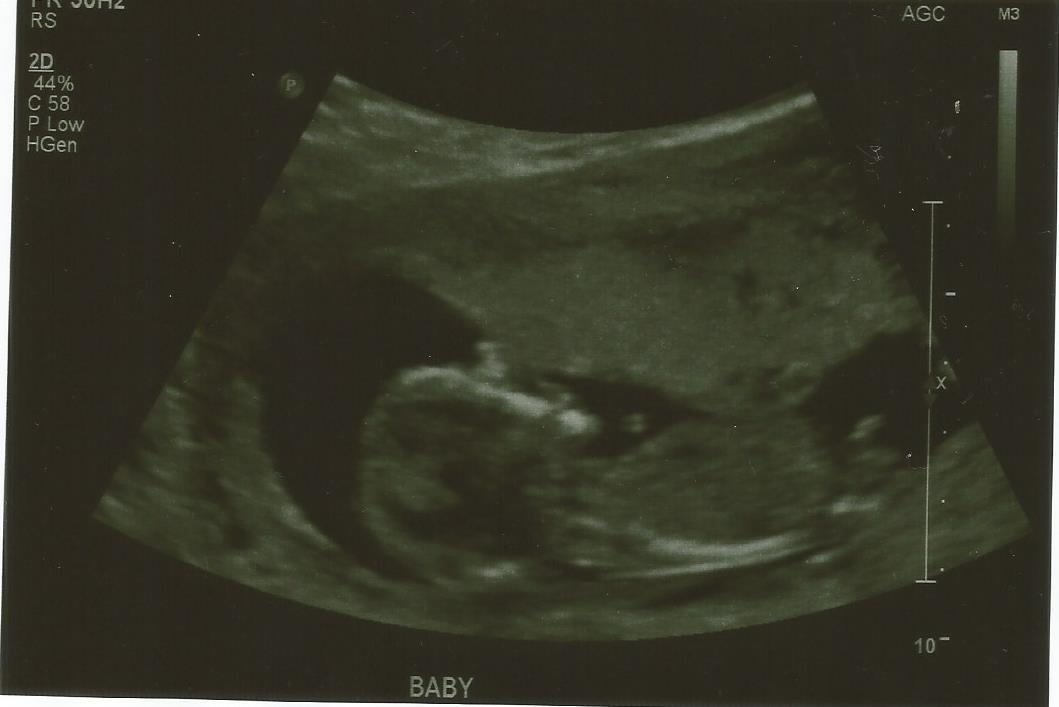

meant to add these pics are 13w 4days

Probably a baby boy

Getting a boy vibe from these too. Did you sway? Curious as I noticed the names as at the bottom of your first pic.

Actually No MiaMelb. We were trying to conceive again since October and I was beginning to lose hope when it happened in April. My period was different before i conceived and I usually would ovulate on day 17 and I did on day 18. Just curious if you think the thing sticking up is a boy nub and nothing else? Me and the husband have been arguing over this lol Funny thing is I told myself that I wanted another girl cause I am so used to girls lol.